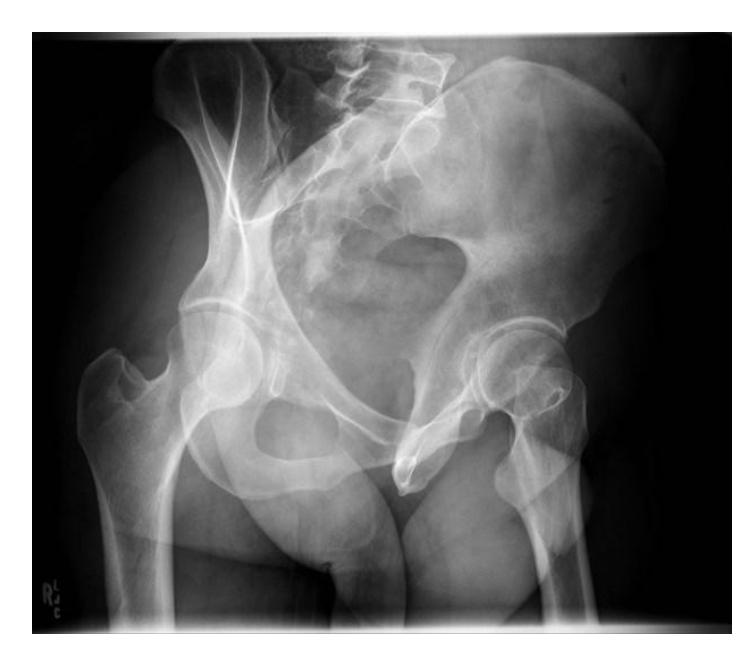

A 13 years old patient, she is known to have idiopathic scoliosis. X-ray pelvis was requested for her.

- 1. Mention the name of the sign seen the X-ray.

- Risser sign

- 2. How it can help in taking decision the management?

- By assessing potential of growth to evaluate potential deformity progression (e.g. scoliosis)

Growth Assessment Signs

Rosserโs sign

1-Describe? Rosserโs sign

2-What is clinical importance of this sign? Measure progress of bony fusion of iliac apophysis. The lower the grade, higher the potential for progression.